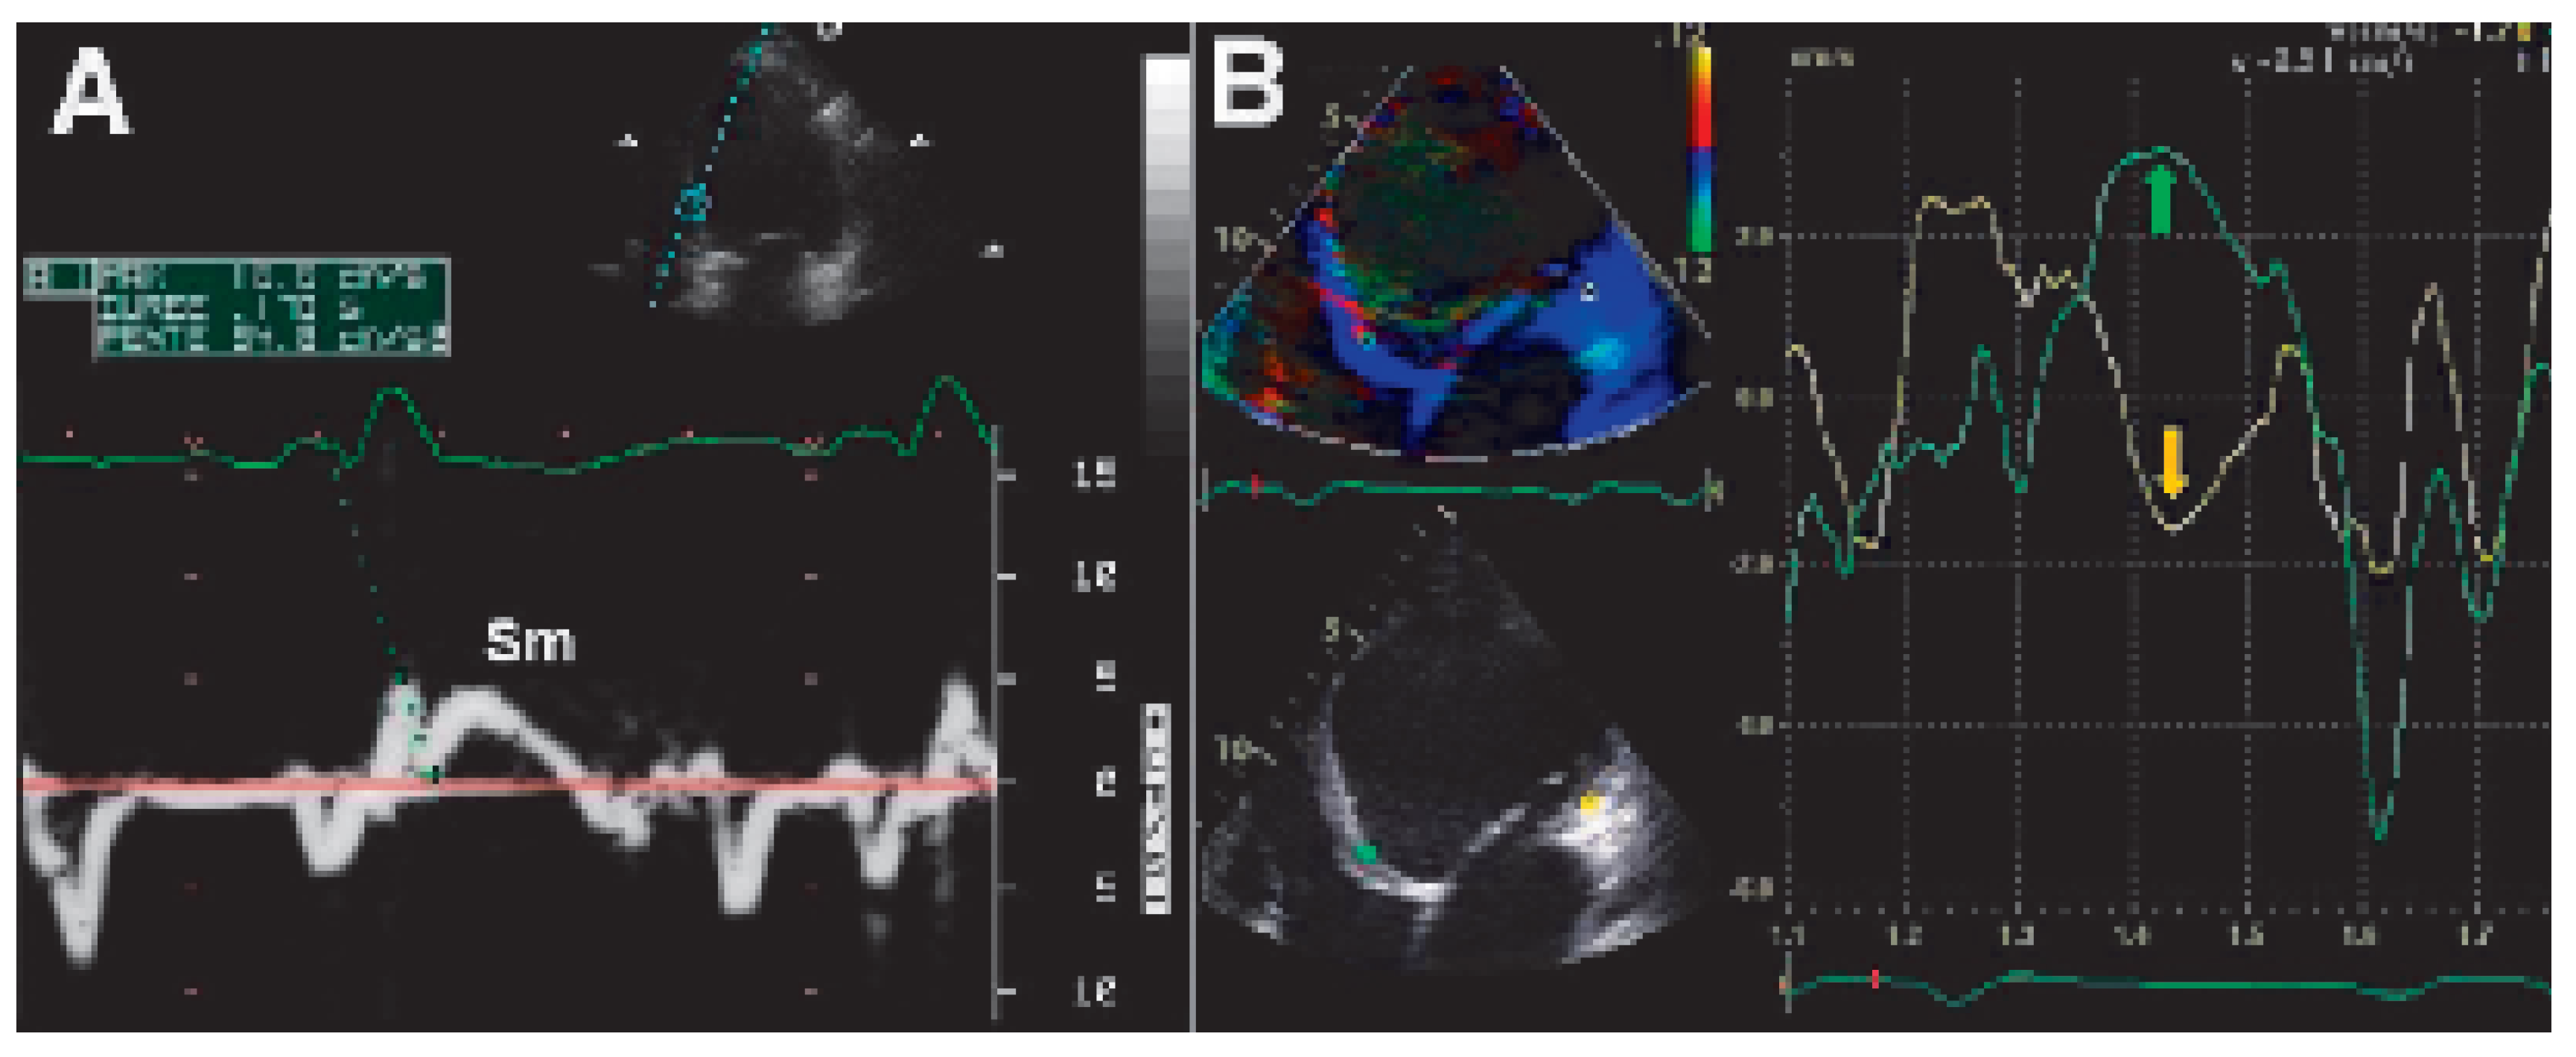

Conventional Doppler echography

![]() |